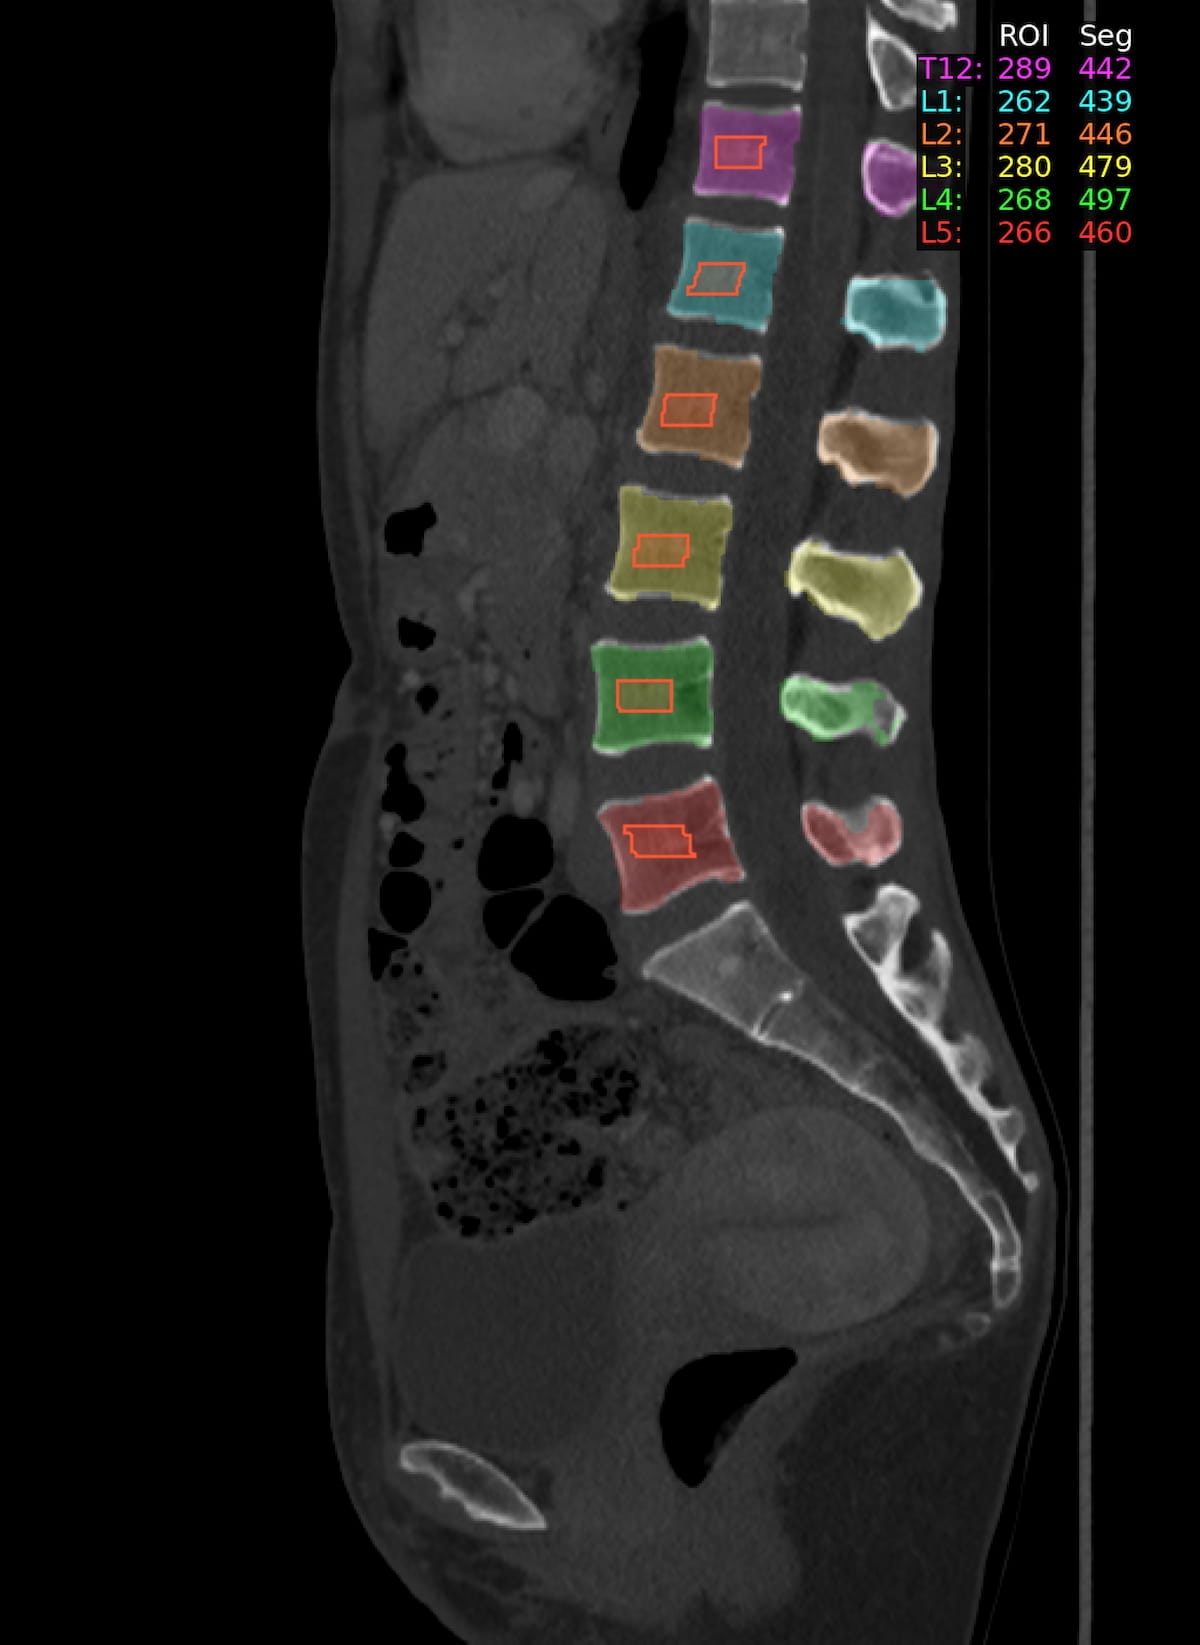

The Bunkerhill BMD software provides AI-automated assessment of bone mineral density from non-contrast abdominal computed tomography scans.

The Food and Drug Administration (FDA) has granted 510(k) clearance for the artificial intelligence (AI)-enabled Bunkerhill BMD software, which provides automated bone mineral density (BMD) assessments of non-contrast abdominal computed tomography (CT) scans.

Cleared for use in adults 30 years of age and older, the